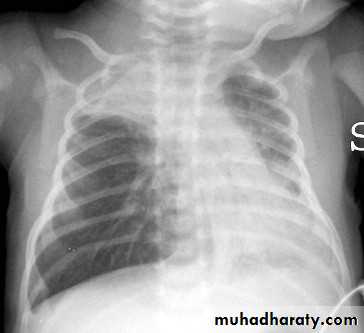

chest radiography reveals hyperinflated lungs with patchy atelectasis.